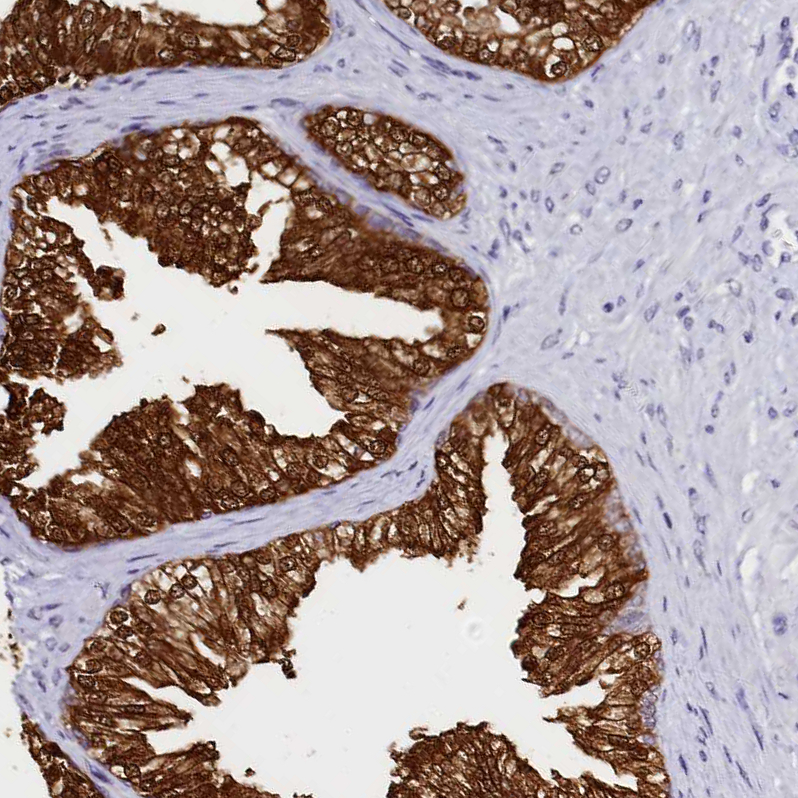

Immunohistochemistry analysis in human prostate and skeletal muscle tissues using HPA040621 antibody. Corresponding SORD RNA-seq data are presented for the same tissues.